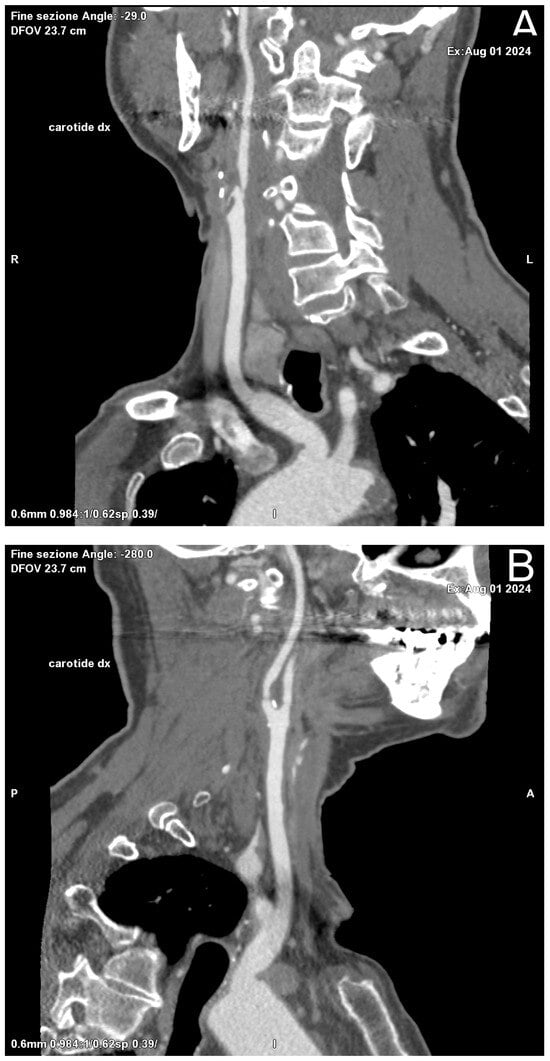

Standard ultrasound, in its B-Mode and Color Doppler applications, is the first-line diagnostic investigation and can be used for both the initial assessment of pathology and follow-up after treatment (Figure 1). It is a widely available technique, free of ionizing radiation, which allows a rapid and dynamic assessment of both the morphologic features of the plaque and any related hemodynamic changes in blood flow, but it is highly dependent on operator experience. Another limitation of ultrasound is the inability to study a high-calcium plaque well [13].

Figure 1. Ultrasound applications in a patient who has received CAS with stent positioning in the right ICA. Color Doppler and Power Doppler modes post-stent show significant hemodynamic stenosis resolution with normalization of VPS values and resistance indices.